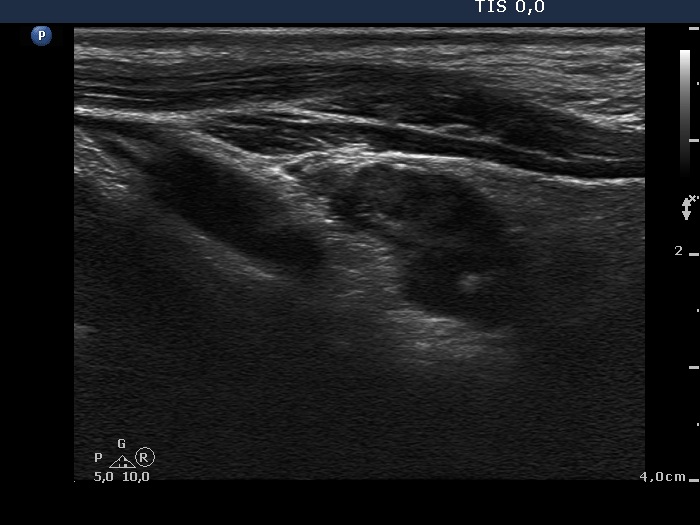

Follow-up examination 7 months after first visit (fourth and fifth third rows):

Clinical presentation: The patient underwent on radioiodine therapy. Post-therapeutic thyroglobulin level was 99.1 ng/mL while 3 months later the TG level fell only to 36.5 ng/mL. An ultrasound examination was initiated.

Palpation: a mass in the lower pole of the left thyroid bed was suspected.

Functional state: TSH 0.06 mIU/L, FT4 27.5 pM/L on daily 175 microgram levothyroxine.

Ultrasonography. There was no parenchyma according to the right thyroid bed. There were two hypoechogenic lesions in the lower pole of the left thyroid bed. Both were irregular in shape and presented cystic degeneration and microcalcifications. There was a reactive-type lymph node ventral to the previously described lesions.

Aspiration cytology was performed but was not diagnostic. The wash-out thyroglobulin-level exceeded 476 ng/mL.

Surgery was performed and 5 lymph nodes were removed. Three of them proved to be metastatic while 2 did benign, reactive-type nodes on histopathology.